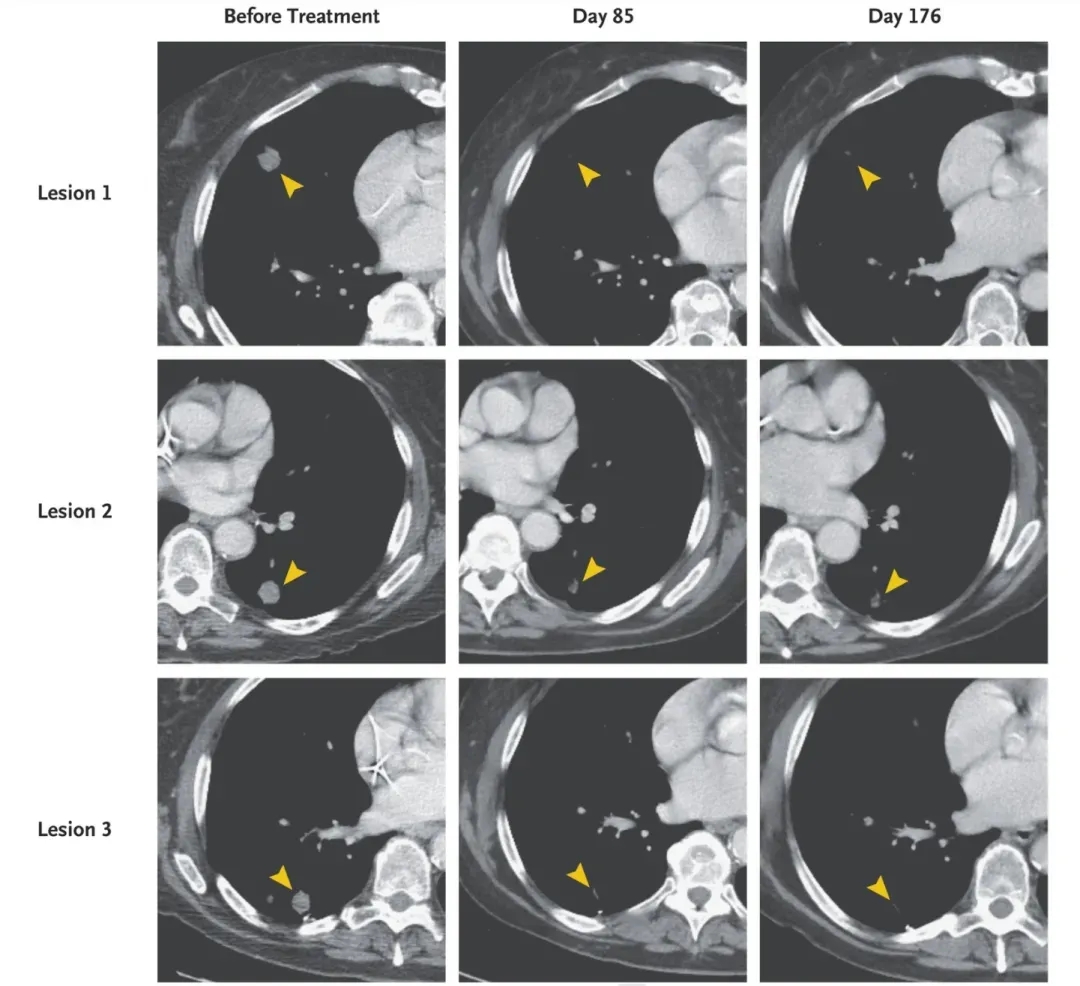

幸运的是,该患者在TCR-T治疗后第21天,血小板及绝对中性粒细胞计数得以恢复;治疗第1个月时计算机断层扫描显示,患者肺转移病灶消退(详见下图);治疗后6个月,部分缓解(PR)率达到72%!

本病例报告再次用数据表明,针对KRAS G12D热点突变的TCR-T疗法,有助于转移性胰腺癌的消退。同时也彰显了TCR-T疗法在治疗胰腺癌和其他表达KRAS G12D的癌症中,具有广阔的应用潜力。

图5 本例胰腺癌患者在TCR-T治疗前后,胸部计算机断层扫描对比

▲图源“NEJM”,版权归原作者所有,如无意中侵犯了知识产权,请联系我们删除